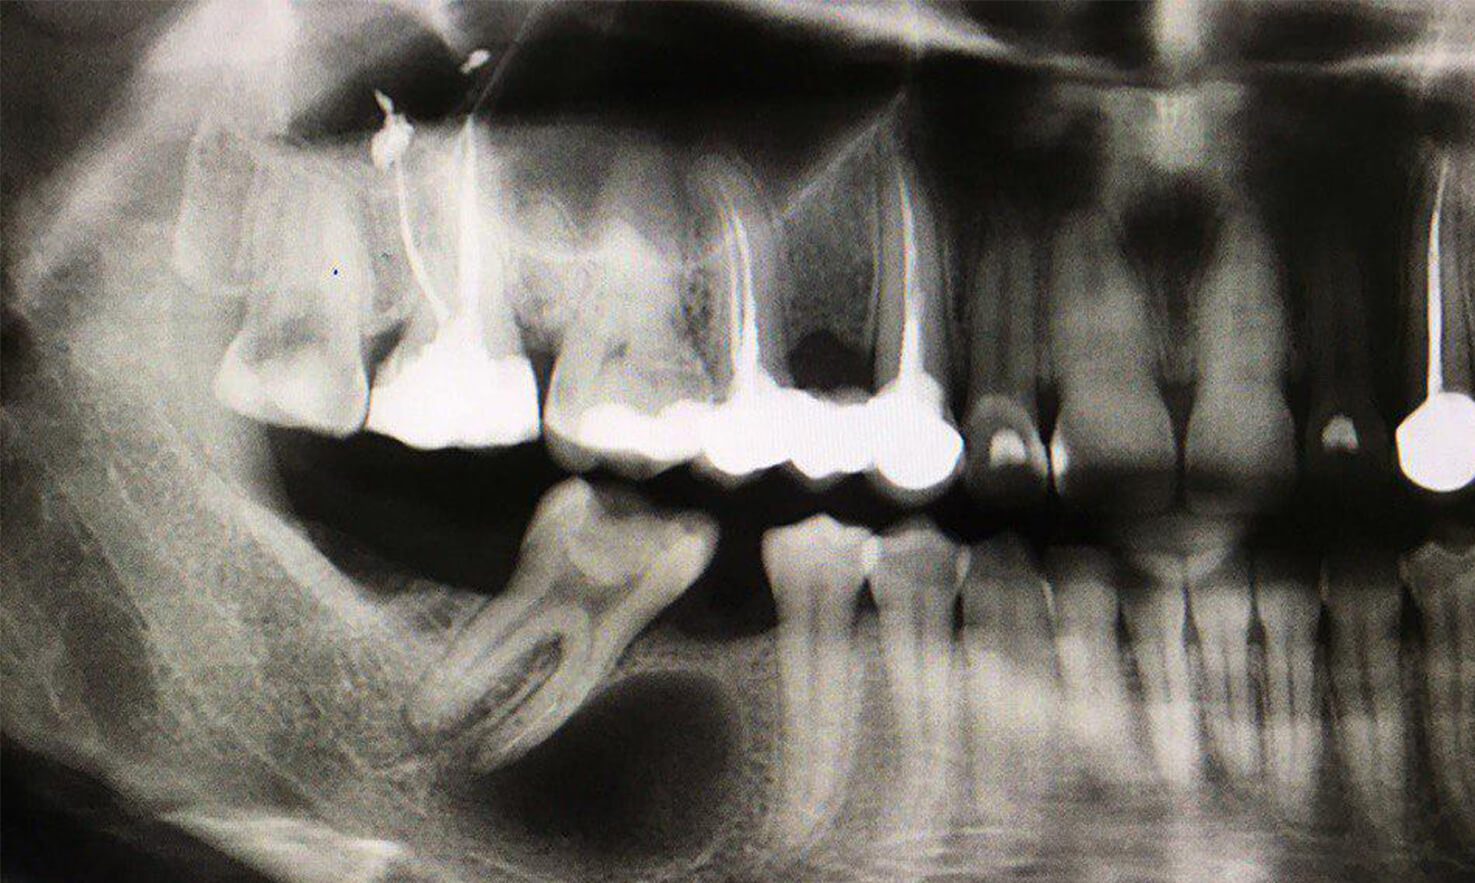

Дентальные снимки и диагностика кариеса